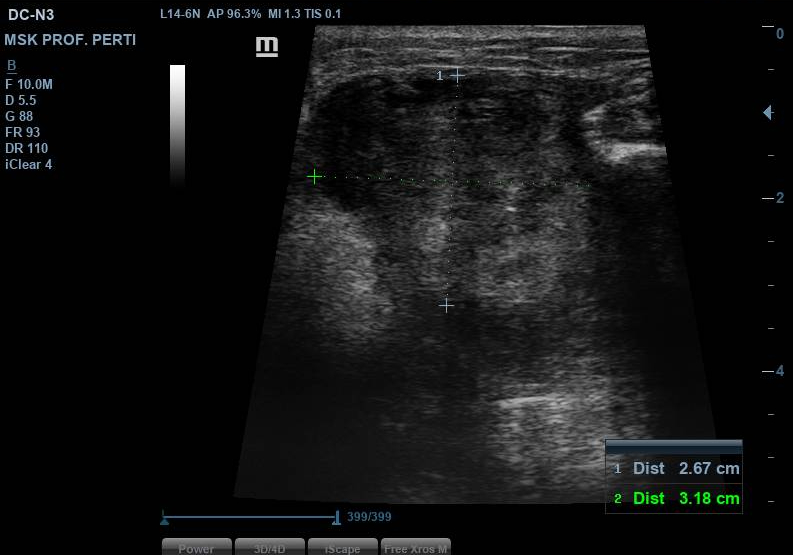

La ecografía muestra una lesión sólida hipoecoica, heterogénea y de contornos irregulares, situada entre la musculatura gemelar lateral y la musculatura peronea, con tamaño aproximado de 2,6–3,2 cm. Presenta áreas anecoicas compatibles con degeneración quística, pequeños focos hiperecogénicos sugestivos de calcificaciones y engrosamiento fascial con pérdida de la arquitectura normal. El estudio Doppler identifica vascularización interna arterial y venosa. Los hallazgos son compatibles con lesión mesenquimal profunda y potencialmente agresiva.

Ecografía hospitalaria: lesión inter e intramuscular mayor (6,7 × 5,5 × 3,6 cm) con contacto con peroné.